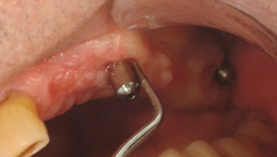

Clasificación de Peri-implantitis5

Temprana: Profundidad de sondaje >4 mm, con sangrado y/o supuración en >2 sitios del implante y pérdida ósea < 25% del largo del implante (Fig. 2)